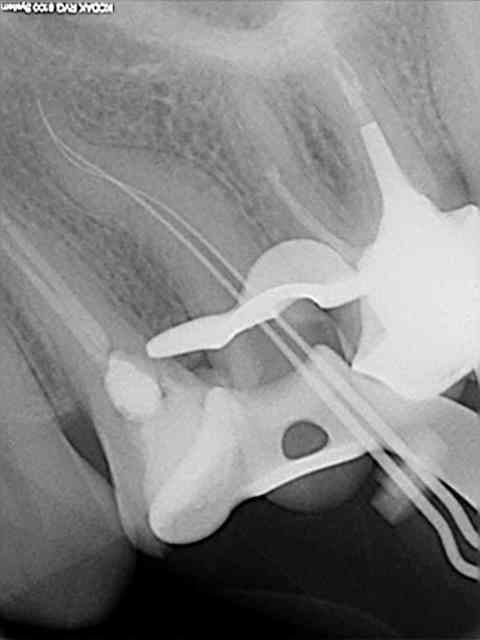

Voici un cas de fracture compacteur.

Utiliser un mac spaden dans ce genre de cas était une bêtise.

Aprés beaucoup d'efforts pour perméabliser les 2 cannaux et les préparer, c'est trop dommage de gacher le résultat en cassant un compacteur.

Cela ne m'a pas gêné pour desobturer et faire l'empreinte pour l'inlay-core, mais la condensation de la gutta au niveau apical n'a pas été terrible.

C'est d'ailleurs un des cas qui m' a décidé à utiliser de temps en temps le thermafill.